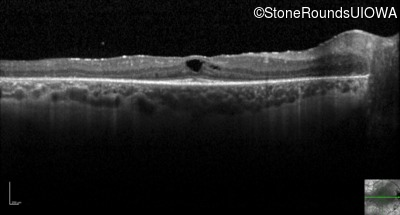

Optical Coherence Tomography - Right - 20/40

Exemplar / OCT Stack

OCT Stack